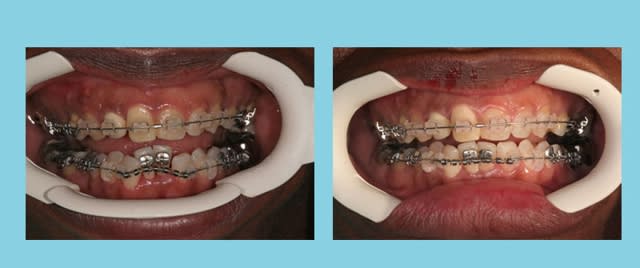

Un petit cas d’encombrement

Age 45 ans

Augmentation de longueur d’arcade = 15 mm.

est-il raisonnable d'augmenter la distance inter-canines ?

Non, extrêmement risqué.

Il y a bien un consensus auquel tout le monde adhère, qui considère qu’on doit éviter d’augmenter la distance inter-canines inférieure.

Damon lui-même le dit dans ses conférences. A l’arcade inférieure, il pratique l’expansion en postérieur et non pas au niveau des canines, comme on peut le constater sur ces trois cas que j’ai pris en photos avec son accord lors d’une de ses dernières conférences.

pour apporter a ce propos:

cependant dans le cas présenté les canines sont linguoversées: il ne faut donc pas prendre en compte la distance cuspide-cuspide puisque expansion ou pas les canines seront redressées mais donc la distance collet-collet:

on se rend alors compte qu'il n'y a pas eu tellement d'expansion que ca et juste une remise en situation Vestibulo lingual des canines à leur juste Version. (peut-etre un peu plus...)

BRAVO alexlop

c'est effectivement un cas de redressement des axes des canines, et je suis encore en dessous de la distance moyenne inter-canine Inf.